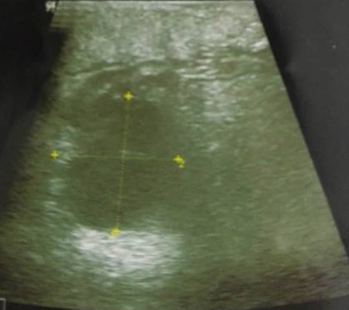

Doppler ultrasound showed no thrombophlebitis but objectified a right popliteal cyst ruptured in the calf (Figure 1 & 2) with a huge fluid collection into the right gastrocnemius muscle layers (Figure 3). The patient was treated with oral and topical nonsteroidal anti-inflammatory drugs for two weeks with favorable outcomes: progressive disappearance of pain and swelling of the calf with return to normal ten days after treatment. The two-week follow-up ultrasound showed complete resorption of the fluid collection in the calf.

Figure 3 Right calf ultrasound: a huge fluid collection into the right gastrocnemius muscle layers.